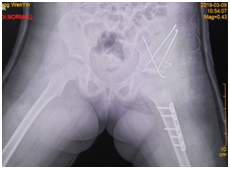

术后DR